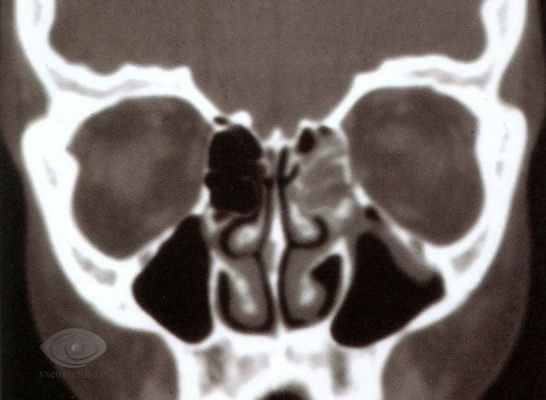

Смещение имплантата отмечено в 1 (1,82%) случае. Пациент был оперирован в 2012 г. по поводу перелома скулоорбитального комплекса и нижней стенки глазницы через 3 нед после травмы. Нами выявлено смещение полимерного имплантата Реперен спустя 6 мес после операции. Данное осложнение было обусловлено наличием обширного мелкооскольчатого перелома нижней стенки орбиты, рубцовыми изменениями орбитальной клетчатки и нижней прямой мышцы, смещением имплантата вследствие рубцевания в верхнечелюстную пазуху. Пациенту потребовалось повторное хирургическое вмешательство в связи с развитием прогрессирующей диплопии и энофтальма (рис. 4—6).

Рис. 4. Пациент Л. Деформация левой орбиты. Состояние через 6 мес после реконструкции нижней стенки левой орбиты. Рис. 5. Пациент Л. КТ (фронтальный срез). Состояние через 6 мес после реконструкции нижней стенки левой орбиты полимерным имплантатом Реперен. Рис. 6. Пациент Л. КТ (сагиттальный срез). Состояние через 6 мес после реконструкции нижней стенки левой орбиты полимерным имплантатом Реперен. Повторная операция, выполненная с применением титанового анатомического эндопротеза Синтез, позволила получить хороший эстетический и функциональный результат (рис. 7, 8). Рис. 7. Пациент Л. После повторной операции. Устранен гипо- и энофтальм. Рис. 8. Пациент Л. КТ (сагиттальный срез) после повторной реконструкции нижней стенки правой орбиты. Анализируя вышеуказанное осложнение, мы обнаружили погрешности в планировании операции: не рассчитан размер дефекта нижней стенки глазницы, а также выбран полимерный имплантат Реперен, который не может обеспечить достаточную жесткость опоры в дистальной зоне.